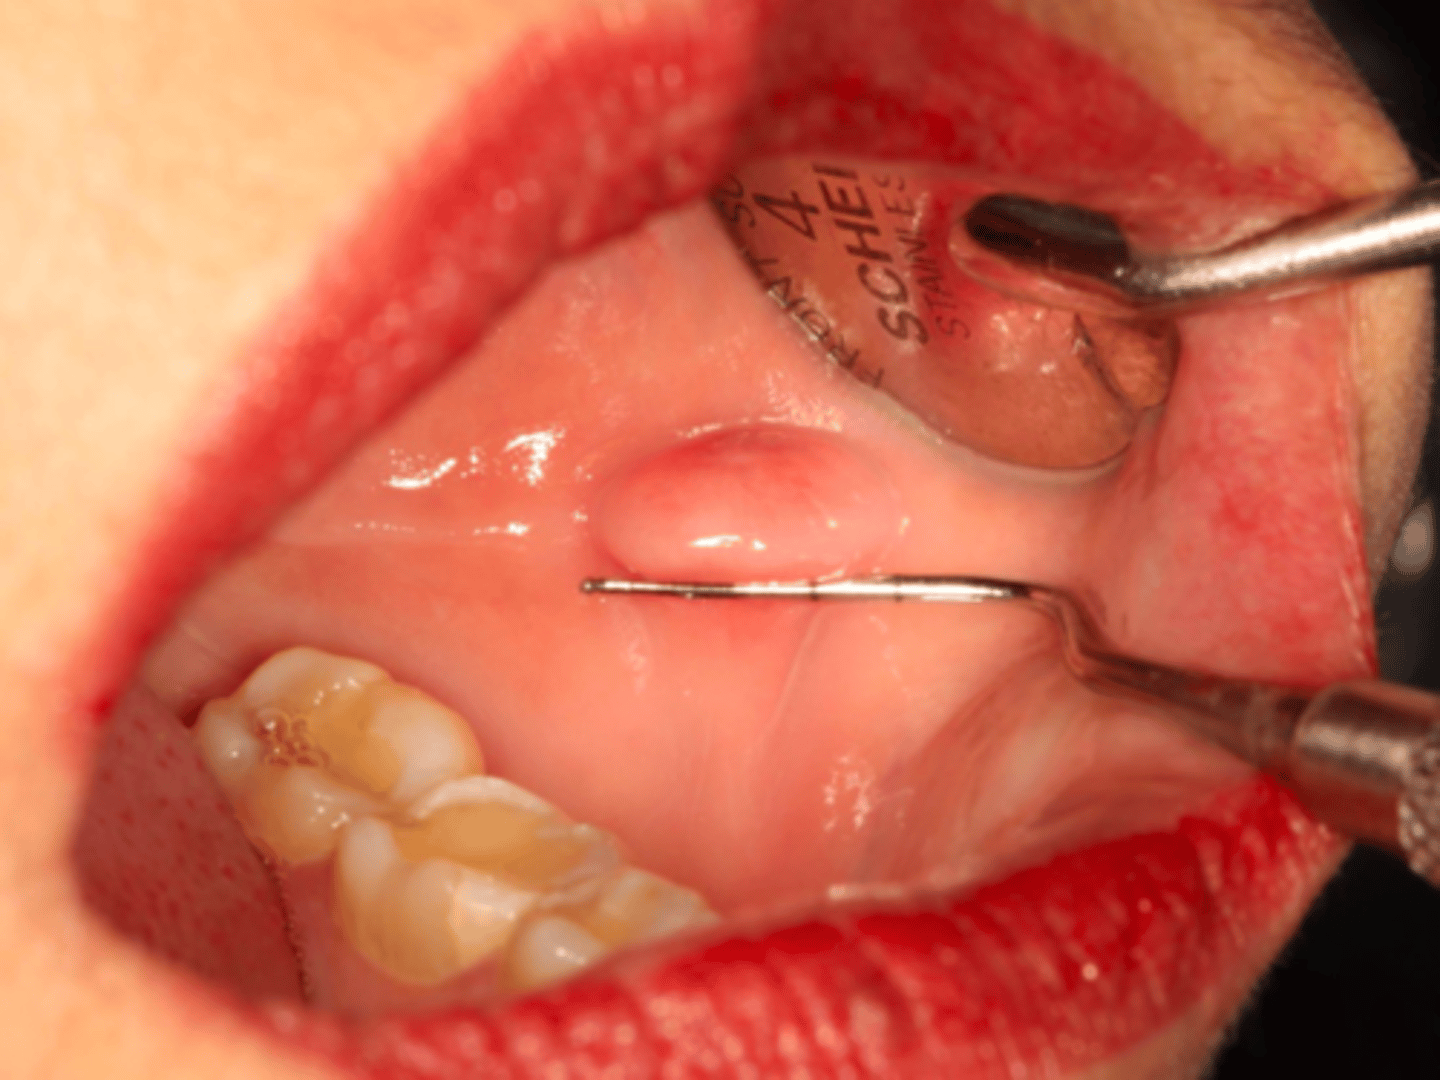

Fibroma

ID the pathology:

-Reactive hyperplasia of fibrous connective tissue

-Results from chronic low-grade irritation

chronic low-grade irritation

what is normally the cause of fibromas?

Fibroma

patient presents with a pink nodule on the buccal mucosa. Patient claims they have always bitten their cheek and started to notice a "bump" forming near the same area. What could this be?

conservative excision

treatment for fibromas:

neoplasia

what needs to be ruled out when diagnosing a fibroma?